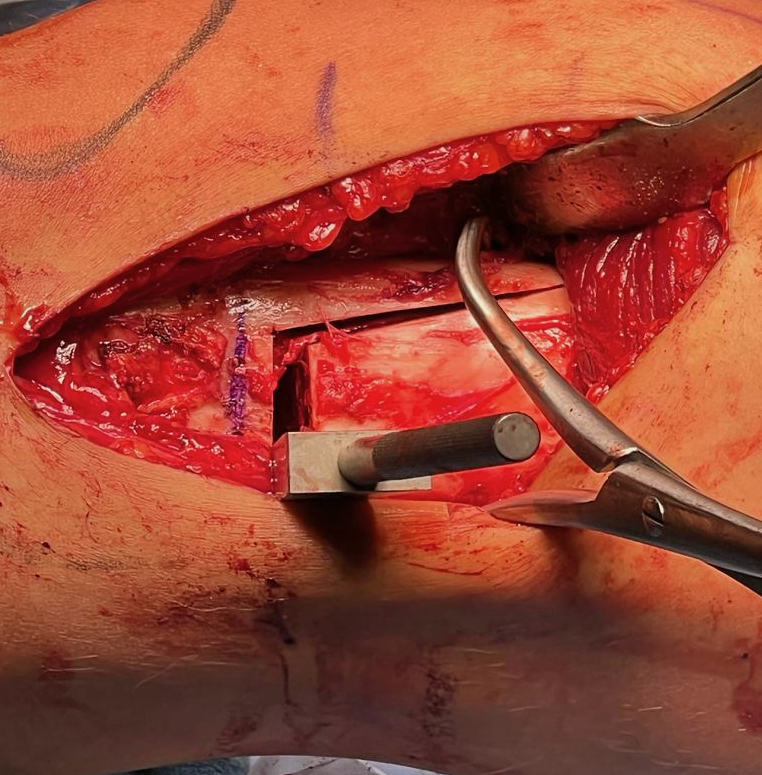

Osteotomy

- insert two K wires for desired wedge

- resect templated wedge

- stop 1 cm short of lateral cortex

- close femoral wedge